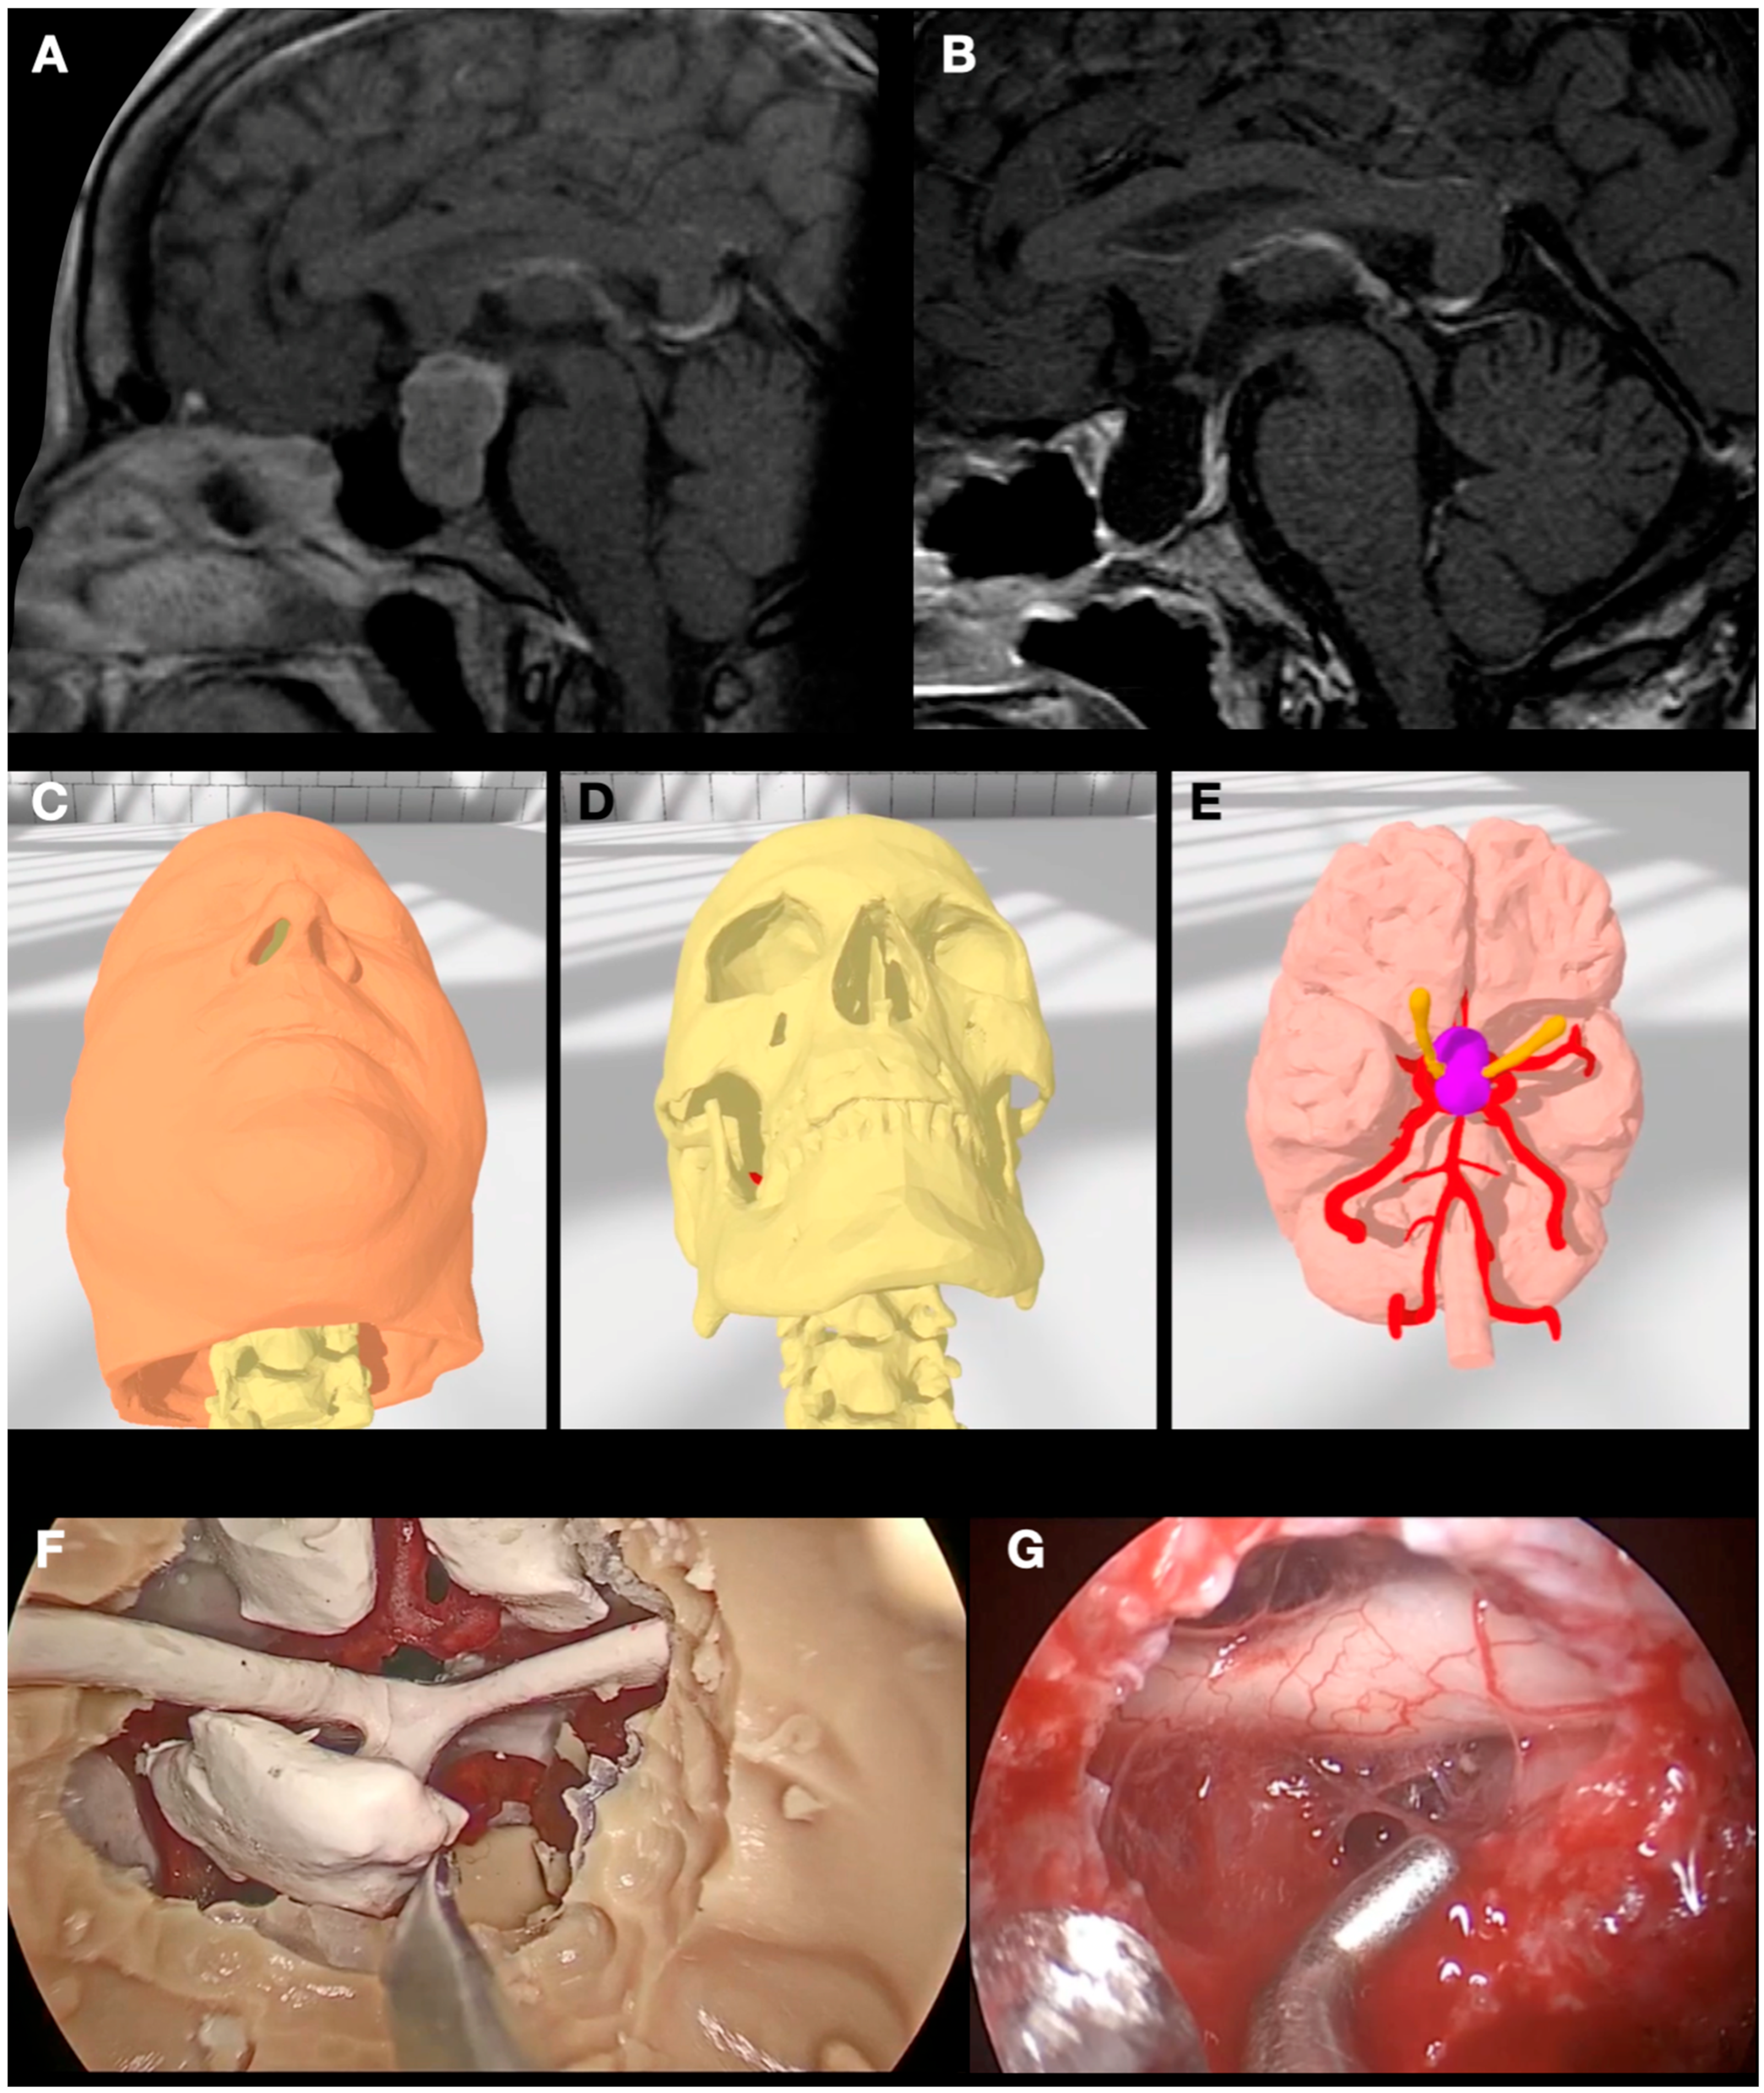

3.4. Case 4: Foramen Magnum Meningioma